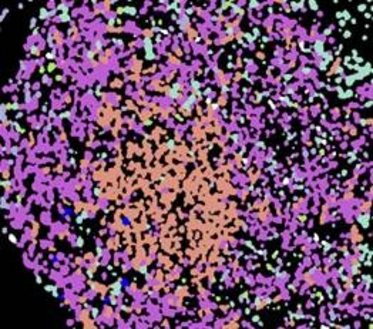

We decompose our tissue analyses by delineating individual cells such as T cells, B cells, plasma cells, macrophages, neutrophils or stromal cells as fibroblasts forming a communicative network within the maintenance of health but also during disease development.

With the help of advanced, high-resolution imaging and tissue analysis, we are developing new methods to recognise diseases at an early stage and treat them in a targeted manner.